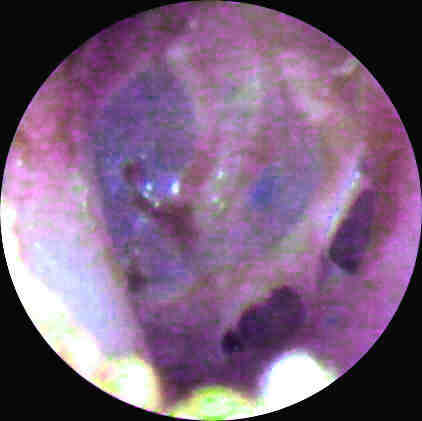

Figure 1. Video otoscopic image of "tympanic cavity impression"

taken in ENT office. Click image for full size view.

The vivid blue cast visible through the tympanic membrane in Figure 1 is the residual silicone impression material filling the middle ear space in intimate contact with the medial surface of the TM. Injection of the material caused a traumatic inferior perforation of the tympanic membrane and subsequently filled the tympanic cavity. Note the hematoma in anterior inferior auditory meatus, probably traumatically induced by the injection gun tip placement.